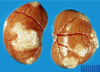

What are the molecular and morphologic changes of the image? ( MDx)

Clinical history and signs: 3 week old puppy, anorexia, dypsnea, abd pain upon palpation, normal rectal temperature

Multifocal, acute renal necrosis and hemorrhage or necrohemorrhagic nephritis

What is the etiology?

Clinical history and signs: 3 week old puppy, anorexia, dypsnea, abd pain upon palpation, normal rectal temperature

Canine herpesvirus-1 (CHV-1)

- red spots are from the virus targeting endothelium